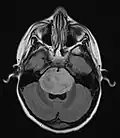

Anatomy